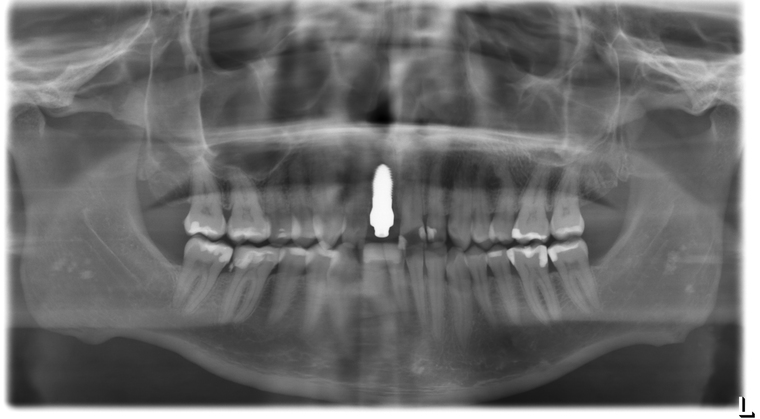

Ein Tätigkeitsschwerpunkt unserer Praxis in Salzburg ist die Implantologie. Wenn ein Zahn fehlt oder entfernt werden muss, sollte immer die Möglichkeit der Implantation im Vordergrund stehen. Ein Implantat verhält sich von den Eigenschaften genau so wie ein natürlicher Zahn. Egal ob nur ein einzelner Zahn vom Zahnarzt ersetzt werden muss oder ein ganzer Kiefer mit festsitzendem Zahnersatz versorgt werden soll, wir finden für Sie eine Möglichkeit, auch wenn die Voraussetzungen ausweglos erscheinen. Wenn möglich versorgen wir unsere Patienten mit Keramikimplantaten. Diese sind immun-neutral und können sehr oft direkt bei der Zahnextraktion eingesetzt werden. Für unsere Patienten ist daher meist nur ein operativer Eingriff notwendig!